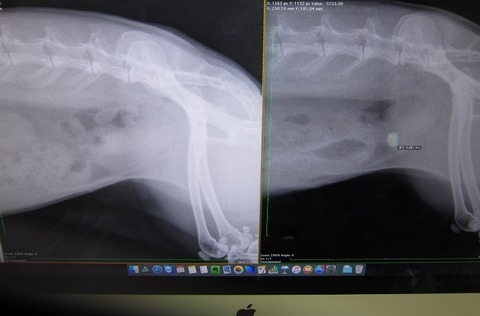

まさかあの9mmの石が出るとは…何で出たんかとかお話の前に、

まずは、石ゼロを確定させるべく早々レントゲンへ。

向かって左が今回、右がこないだ。

光の加減で膀胱全体が白っぽく見えますが石はありませんっ

石はありませんっ